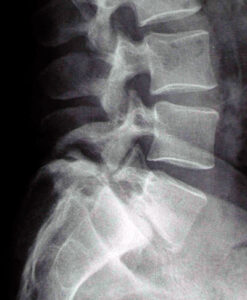

Spondilolistesi Degenerativa

Cos’è

La spondilolistesi è lo scivolamento in avanti di una vertebra rispetto a quella sottostante, più frequentemente a livello L4-L5.

- Dolore lombare localizzato e rigidità

- Dolore irradiato o formicolio alle gambe

- Possibile debolezza muscolare se vi è compressione nervosa

Cause

Nella forma degenerativa, è dovuta all’usura dei dischi e delle articolazioni posteriori che compromettono la stabilità della colonna.